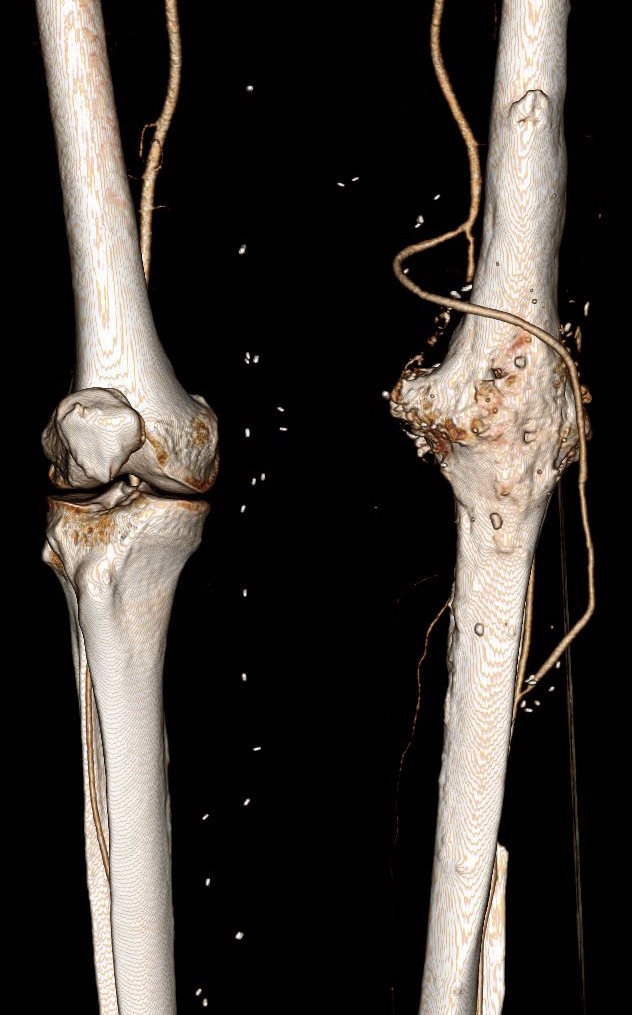

On examination, he had heavy scarring in both groins from prior open incisions healed by secondary intention, a midline laparotomy incision. He had weak bilateral axillary and brachial artery pulses. He had no pulses in either leg. The right foot had gangrene of the distal phalanx of the third toe. The both feet were anemic and painful -the left foot had more dependent rubor. Pulse volume recordings were flat in both legs. TCPO2 was in the 20-40mmHg range at the thighs bilaterally suggesting reduced potential for healing an above knee amputation. Vein mapping showed no suitable saphenous vein in either leg. CTA (figure below) showed both external iliac arteries to be occluded or absent and the common femoral arteries to be occluded or missing bilaterally.

The left femoral bifurcation was preserved and the left SFA was patent into small underfilled tibial vessels. On the right, there was an isolated segment of profunda femoral artery that reconstituted from pelvic collaterals. The right below knee popliteal artery reconstituted and had underfilled but patent three vessel runoff (figure below).